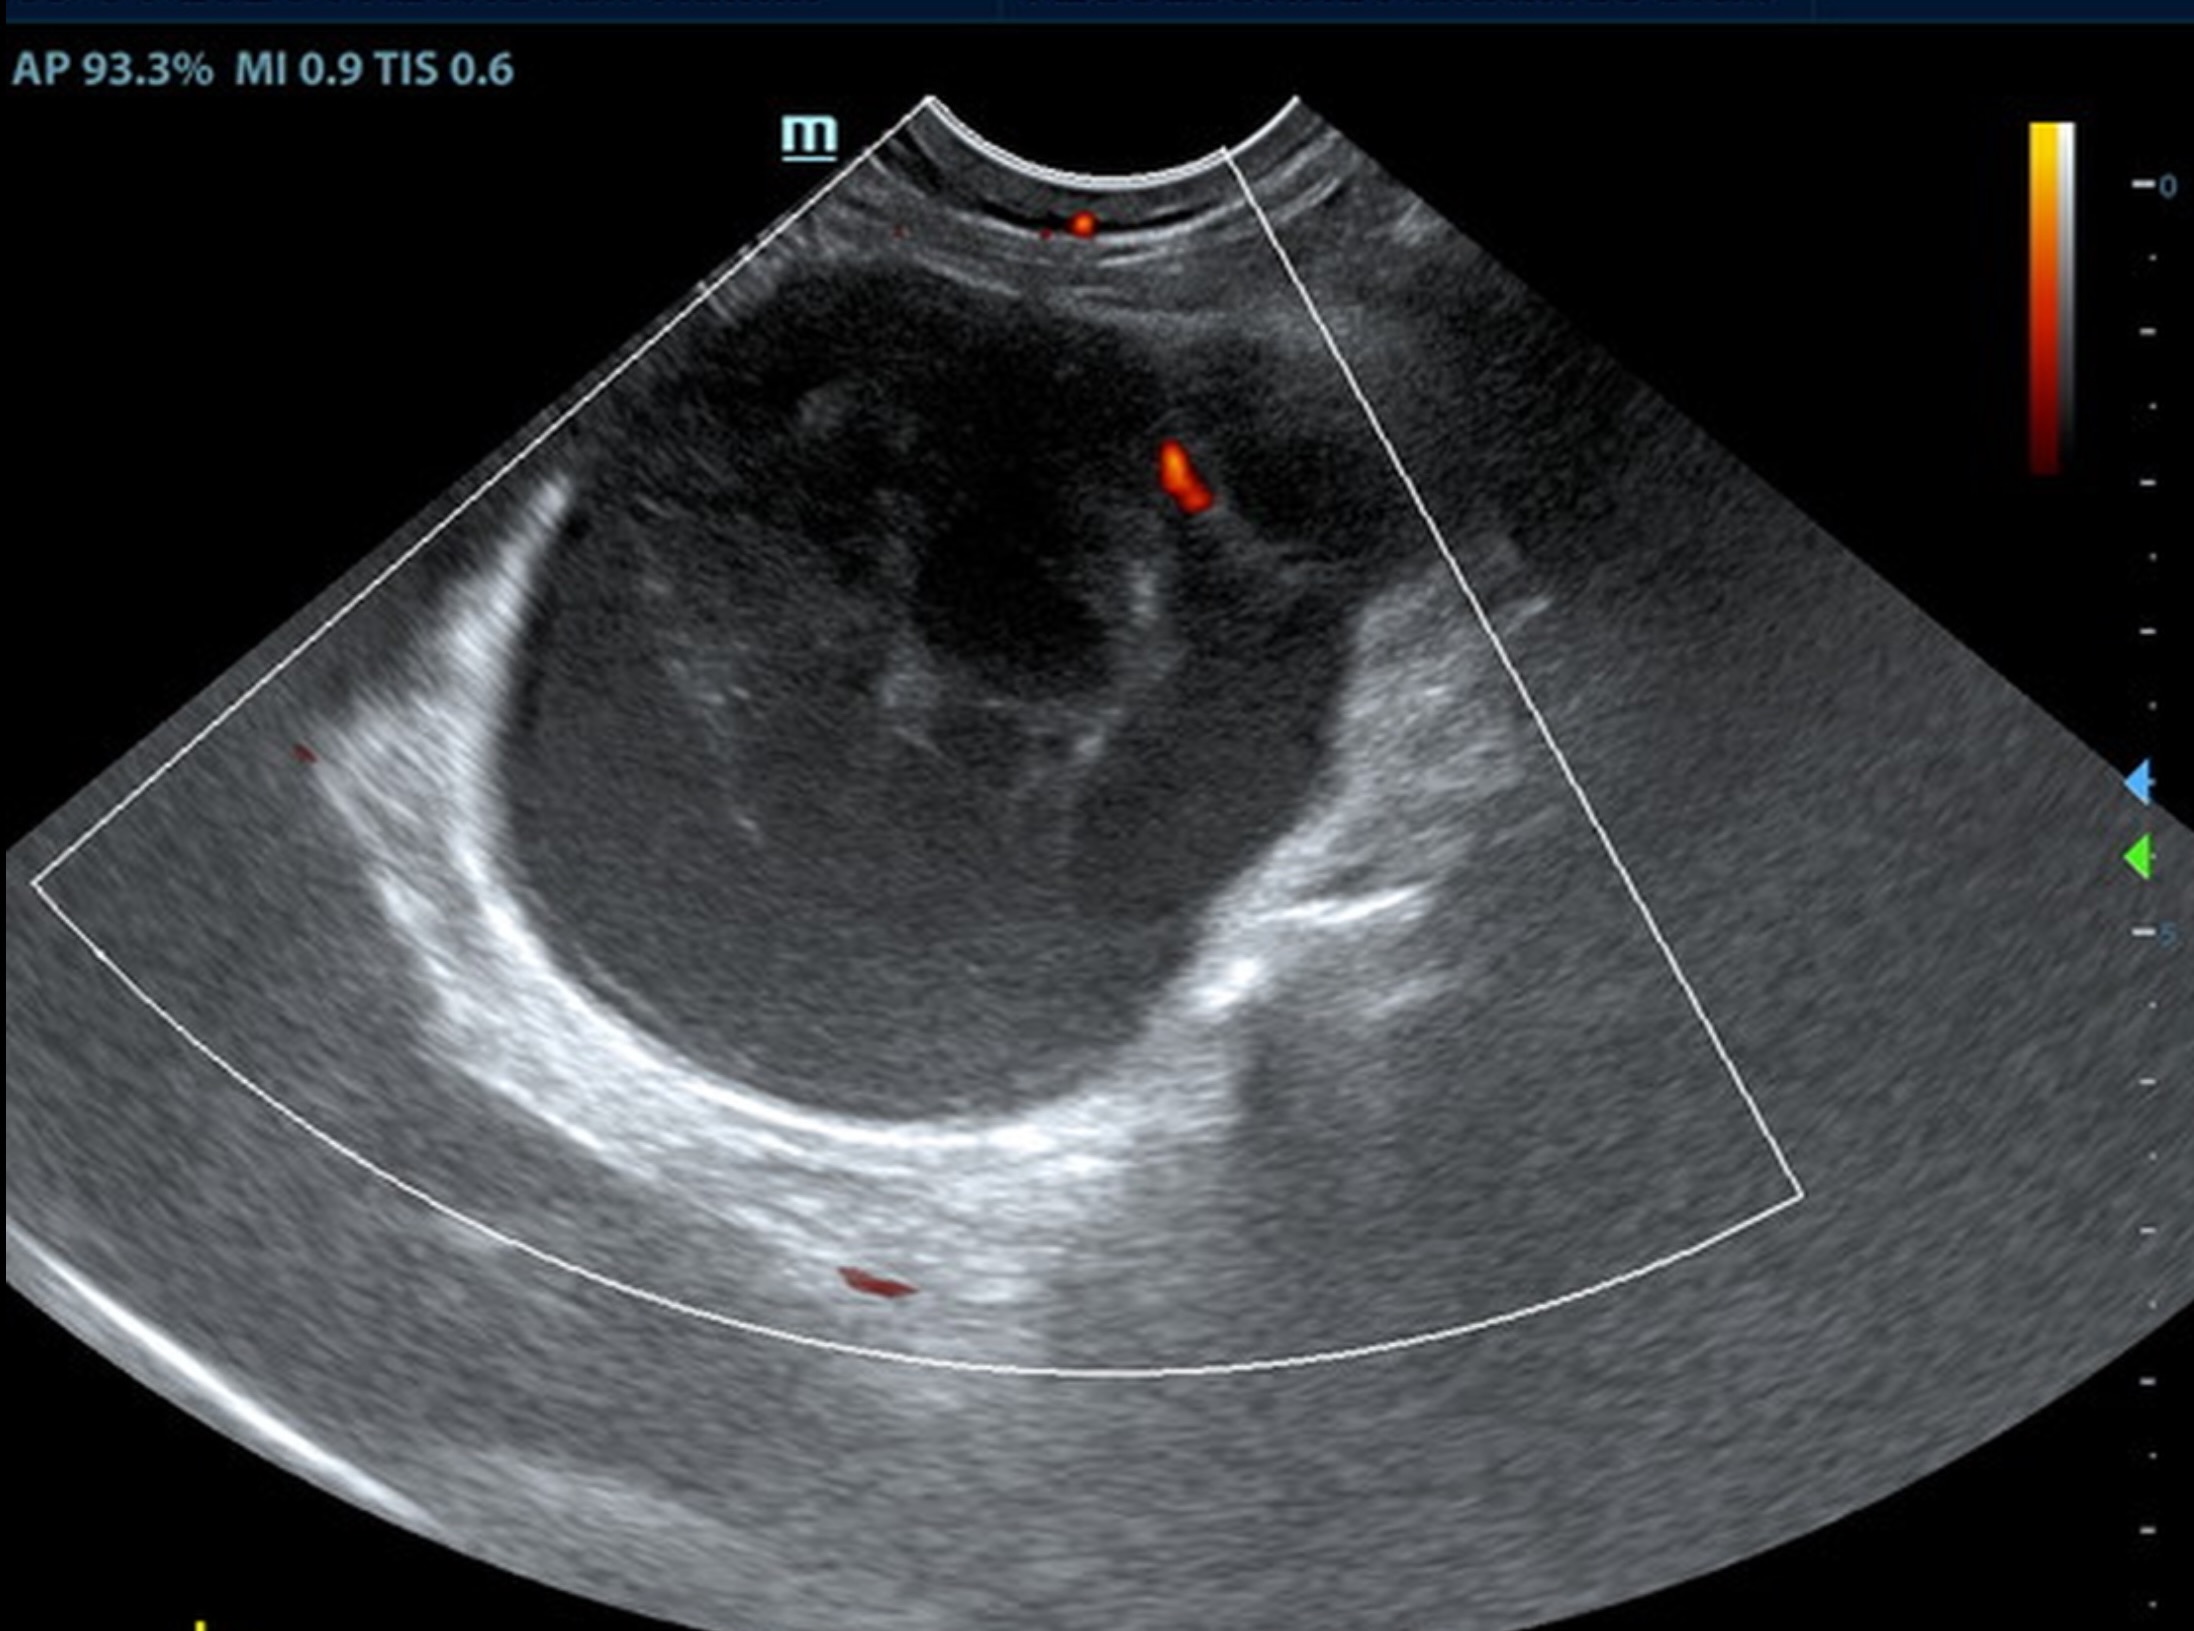

A 6.5 cm hypoechoic abscess was noted in the region of the left pancreatic limb with hyperechoic granulation bed and regional inflammation. The abscess was largely non-vascular. One minor portion of color flow uptake noted within the abscess.

• Large left-sided pancreatic abscess.

Rapid surgical intervention recommended. Ultrasound guided drainage could be considered. However, there is significant potential for leakage, given the turgid pattern of the abscessation. The remainder of the abdomen was unremarkable other than age related changes. Culture and sensitivity indicated. No evidence nor suspicion of neoplasia.